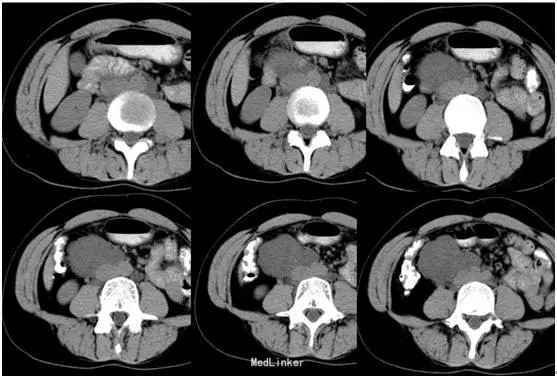

腹部平坦,未见胃肠型及蠕动波,无腹壁静脉曲张,腹软,下腹部轻度压痛,无反跳痛,下腹部扪及一包块,大小约7.5×6cm,质地硬,位置固定,移动性浊音阴性,肠鸣音正常。T 37.5°,P62次/分,R21次/分,Bp140/86mmHg。MR平扫及增强示:中下腹偏右侧见类圆形等长T1长T2异常信号,FS-T2WI呈高信号,DWI(b=800)呈高信号,相应ADC图呈低信号,边界尚清,周围组织受压但未受侵及,注入GD-DTPA后病变强化。

初步诊断:腹膜后肿瘤。行剖腹探查术+腹膜后肿瘤切除术。术后病理:(腹膜后)淋巴管肌瘤病。免疫组化:Vim +、SMA +、HMB-45 少数散在+、Ki-67 5%、MelanA -、ER -、PR -;扁平上皮:CD34 +、CD31部分+、D2-40灶性+。